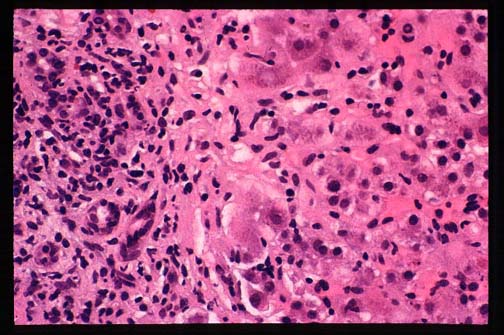

Fig. 9-1-3-Autoimmune hepatitis.

Lobular inflammation and focal necrosis.